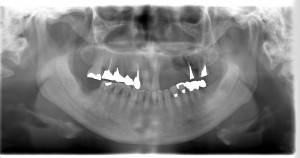

56歳 女性 インプラント症例

56歳 女性 M.H様

左上の前歯3本が歯周病で抜けてしまったため、インプラント治療を希望し来院された患者様です。

3本のインプラント施術を行いました。

その後、右下の1番奥の歯と右上の奥から2番目の歯が歯周病によって、抜かなければならなくなったため入れ歯・ブリッジ・インプラントを欠損部の治療法としてご提案した結果前回の治療の結果に満足されたため、今回もインプラント治療を行うことにしました。